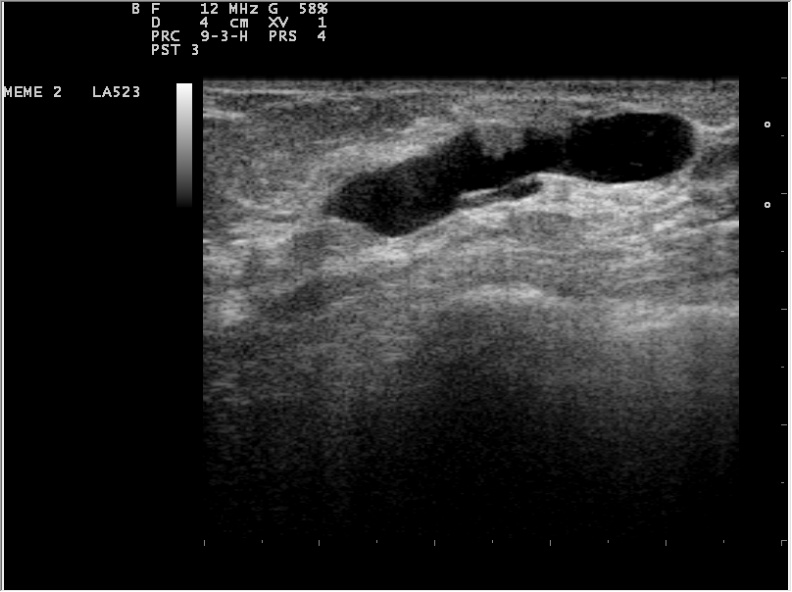

Mammary Duct Ectasia

Mammary duct ectasia is a rare condition where there is inflammation with dilation (ectasia) of the subareolar ducts.

Mammary duct ectasia typically occurs in postmenopausal women who are multiparous.

Mammary duct ectasia presents as a periareolar mass with green-brown nipple discharge (inflammatory debris).

Histology of mammary duct ectasia reveals chronic inflammation with plasma cells.